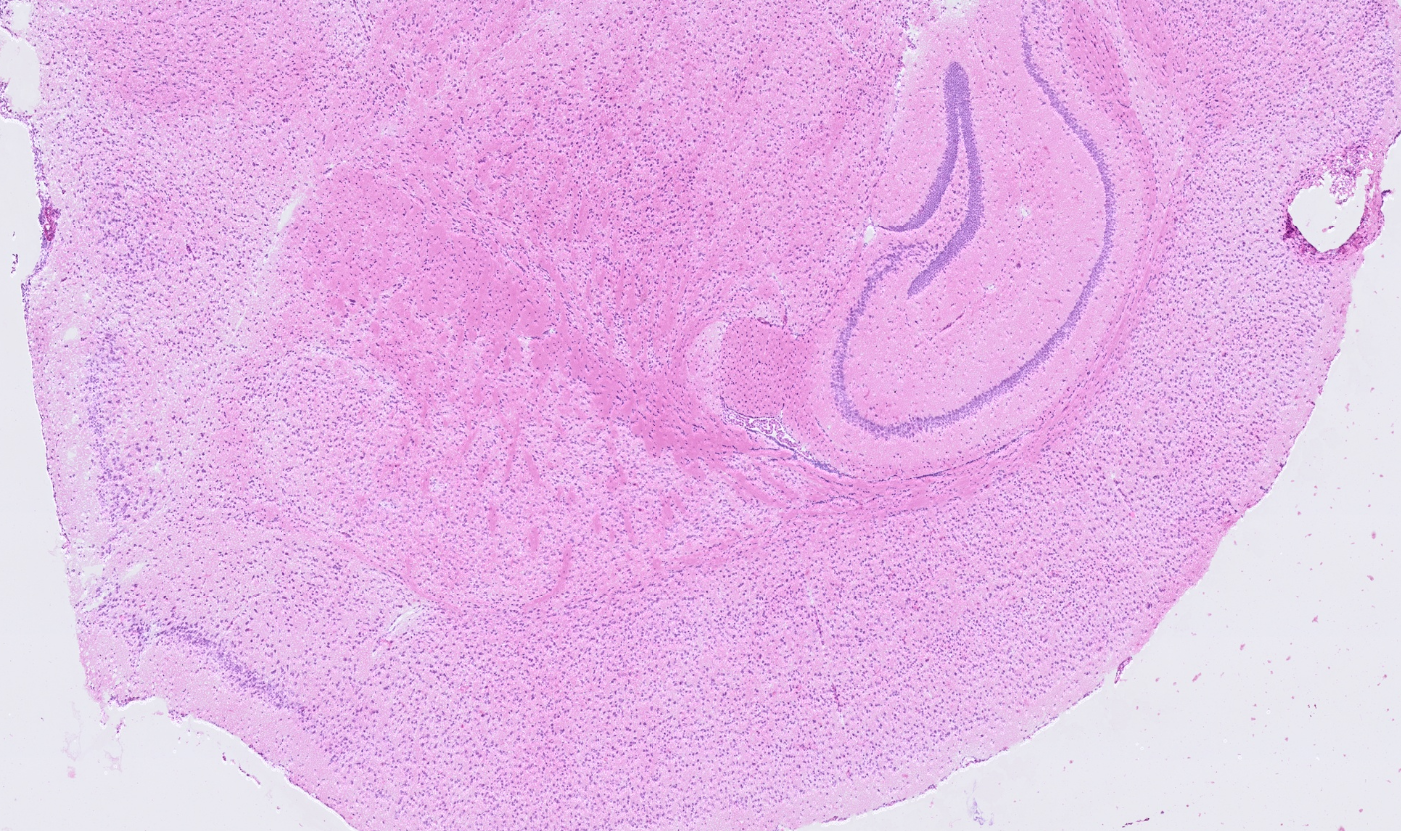

Applicability across many tissue types

The segmentation module is designed to generalize across a wide range of biological tissues. Below are representative benchmark results based on 10x Genomics demo datasets:

Lymph node